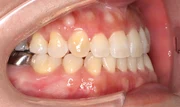

難しいケース3.下顎前突(反対咬合・受け口)

下の前歯や下顎が上の前歯よりも前にでているかみ合わせ。受け口が子供の頃よりコンプレックスで目立たない装置での治療を希望された患者さま。22ヶ月という治療期間を経てかみ合わせと口元が改善しました。